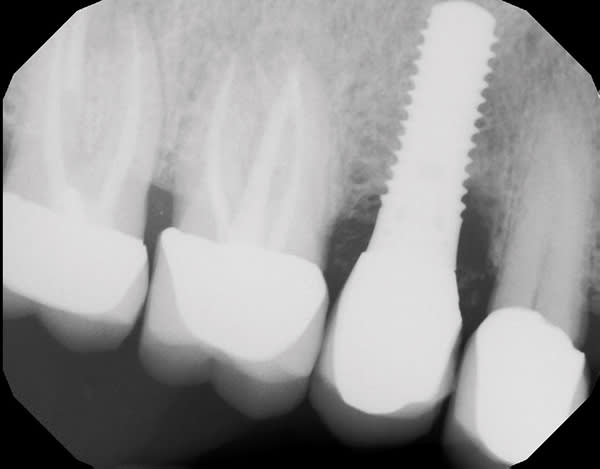

A 63-year-old male patient was referred in 2015 after a routine cleaning at his restorative dentist revealed pocketing and heavy bleeding on probing (BOP) around an implant in site No. 4. The implant (Straumann RN TE) had been placed in 2003 under the author's care due to a previous root fracture of the endodontically treated tooth No. 4, which had been extracted 6 months prior to presentation. The final implant crown was cemented with a polycarboxylate cement in 2003. The patient was highly compliant under his general dentist's care with regular 6-month prophylaxes. In 2015, the patient presented as a healthy non-smoker with a controlled medical history of atrial fibrillation and high cholesterol. Parafunctional habits were contributory to the failed tooth. The patient was diagnosed with site-specific beginning-to-moderate peri-implantitis around No. 4. LAPIP treatment using the PerioLase® MVP-7™ Nd:YAG laser (Millennium Dental Technologies, lanap.com) was performed. At 2 weeks' follow-up, the patient reported 0 out of 10 on a discomfort scale. He maintained good plaque control and returned to his restorative dentist's care after 6 months of healing for alternating periodontal maintenance visits every 3 months. At 7 years' postoperative, the peri-implant tissues associated with No. 4 were healthy with ≤4 mm probing depths and light BOP.